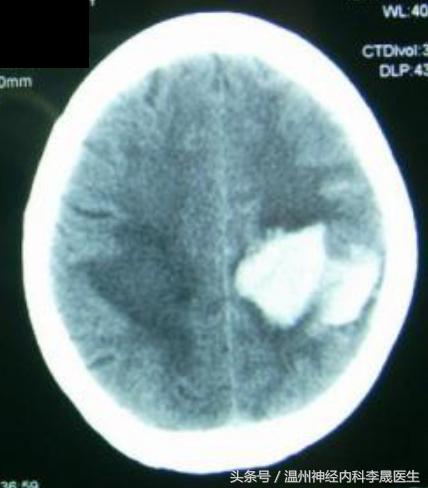

2.脑叶出血

常由脑AVM、Moyamoya病、脑淀粉样血管病、肿瘤卒中等所致,占5~10%

以顶叶最常见,其次为颞叶、枕叶、额叶,可有多发脑叶出血。 临床可表现为头痛呕吐,癫痫发作较多,肢体瘫痪较轻,昏迷少;根据累及脑叶的不同,出现局灶性定位症状和体征。

(A)左侧颞叶大出血压迫同侧侧脑室;(2)较小的右侧颞叶出血